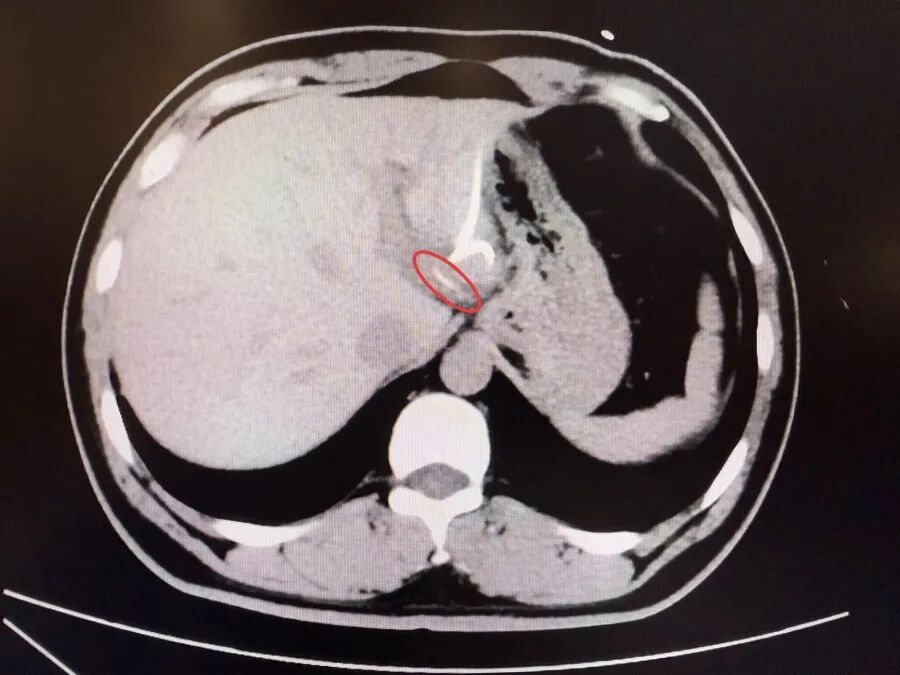

直到行CT檢查時,醫生才驚訝地發現——肝臟左葉靠近胃賁門處,竟有一條細長的高密度影,形似魚刺。原來,那根魚刺在吞咽厚穿透了胃壁,從賁門區域「鑽」入肝臟,引發感染與膿腫。在簡單進行肝膿腫介入穿刺引流后,當地外科醫生評估后認為,要徹底清除異物,需要進行左半肝切除手術,但這對於李先生來說,創傷大、風險高,他難以接受。